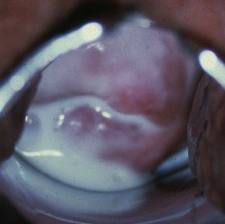

A patient complaining of discharge has this finding on pelvic exam. What is the most appropriate diagnostic test?

Wet mount to look for trich

(Colpitis macularis = “strawberry cervix”; think trich!!)